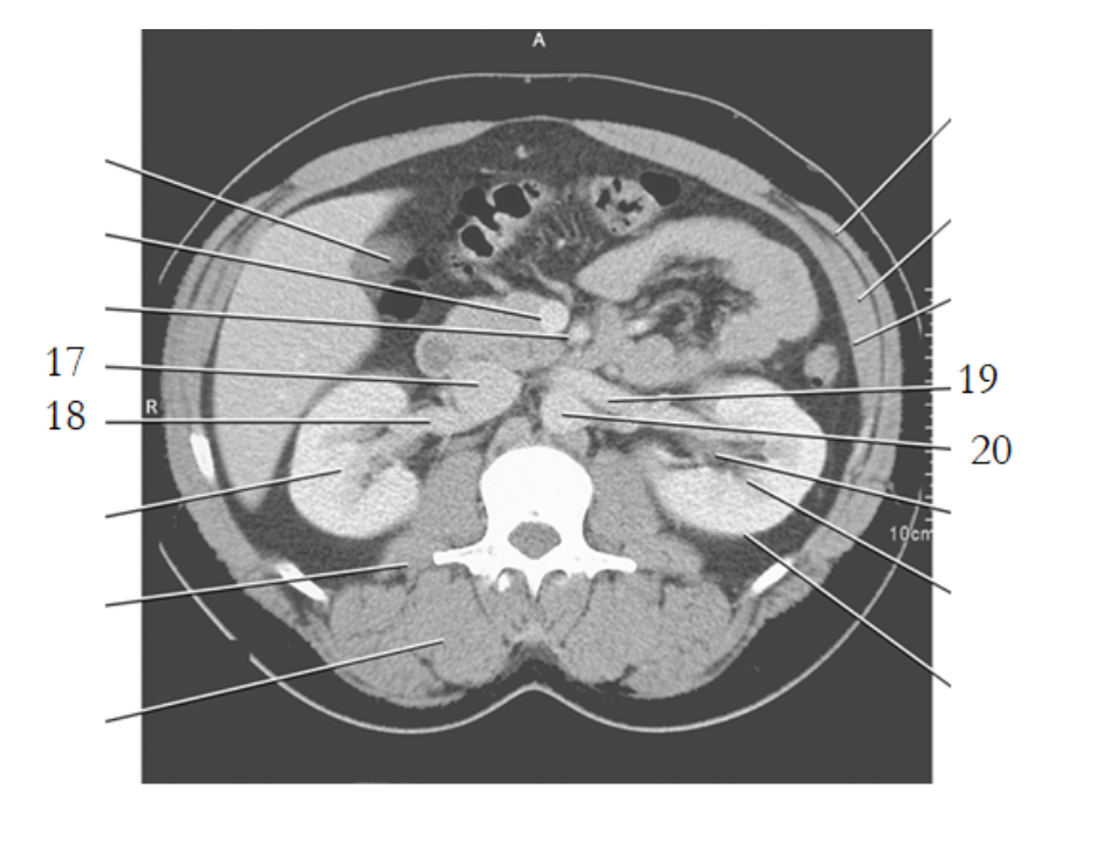

20

aorta

24

19

left renal vein

small bowel

21

large bowel